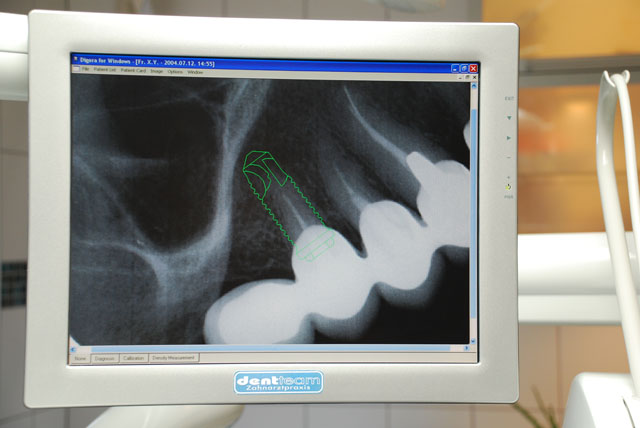

Röntgengerät mit Digitalen Bildern

Im digitalen Röntgengerät intensiviert der Bildverstärker sogar schwache Bestrahlung. Das auf dem Monitor erscheinende Bild kann mithilfe eines Computers weiter verfeinert werden. So ist das Bild schärfer und kontrastreicher. Einzelne Stellen können getrennt filtriert werden - mit Konzentrierung auf Weichstellen oder auf den Knochen. Mit der Bildvergrößerung werden auch verdeckte, winzige Stellen sichtbar. Auf dem Bild können genaue Messungen vorgenommen und ein Operationsplan aufgestellt werden. Das Gerät ermöglicht Durchschnitte in allen Richtungen.Es ist auch möglich, Bildteile herzustellen, über einen engeren Bereich mit minderer Bestrahlung. Das digitale Röntgenbild liefert mehr Information bei minderer Strahlungsbelastung.

Digitale Computer Röntgenbilder